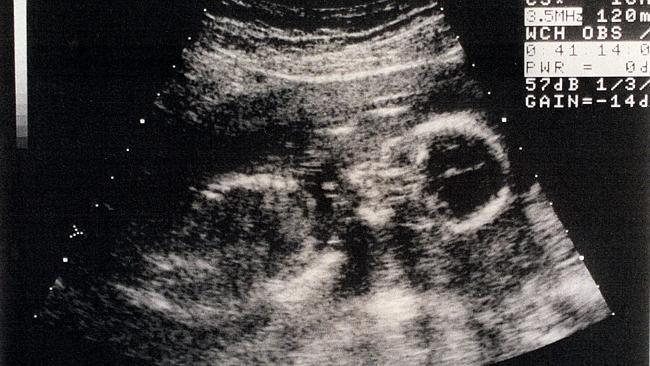

Scientists have discovered that babies in the womb, as young as 16 weeks, respond to music by ‘dancing’.

“The foetuses responded to the music by moving their mouths or their tongues as if they wanted to speak or sing,” said one of the researchers, Marisa Lopez-Teijon. The research has been published in journal of the British Medical Ultrasound Society, Ultrasound.

What this means is that babies’ cognitive faculties, creative faculties, and listening and communication skills are more highly developed at 16 weeks than previously thought.